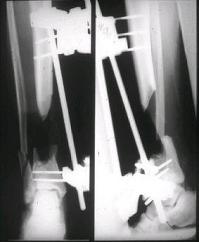

Может, данное наблюдение поможет в принятии решений в подобных ситуациях.

Огнестрельный дефект костей и передней группы мышц, поступил с юнилатеральным аппаратом, стабильность плохая, из раны обильное гнойное

отделяемое. #1;#2. Стержневой апп. снят, наложен апп. Илизарова, дренажно-ирригационная система промывки раны. #3; #4. После стихания инфекции,

аппаратом постепенно создана рекурвация для сближения контактов мышц (сухожилий) передней группы голени. #5;#6. Наложен шов на сухожлилия М.

Tibialis anterior и M extensor digitorum L. Одновременно компактотомия костей голени в В/3 для замешение дефекта костей. #7;#8. Постепенно

исправлена ось и возмещен дефект. В результате восстановление тыльной флекcии стопы и функции конечности. #9;#10;#11

После пары Irrigation& Debridment с вакуумом можно провести окончательную фиксацию интрамедуллярным методом. Чем быстрее, тем лучше, потому что сроки нахождения наружных фиксаторов на конечности тоже имеют значение, риск осложнения увеличивается после длительного пребывания наружного фиксатора.

Открытые переломы, если имеется хороший доступ из раны можно сопоставить и зафиксировать первично пластиной, потому что несопоставленные переломы намного труднее репонируется в поздние сроки. Активизация больного за счет стабилизации кости благоприятно влияет на сращение, а также облегчается манипуляция по закрытию дефекта.

здесь случай с политравмой, перелом зафиксирован наружным фиксатором, после третьей irrigation&debridment фиксация бедра пластиной с последующей кожной пластикой.